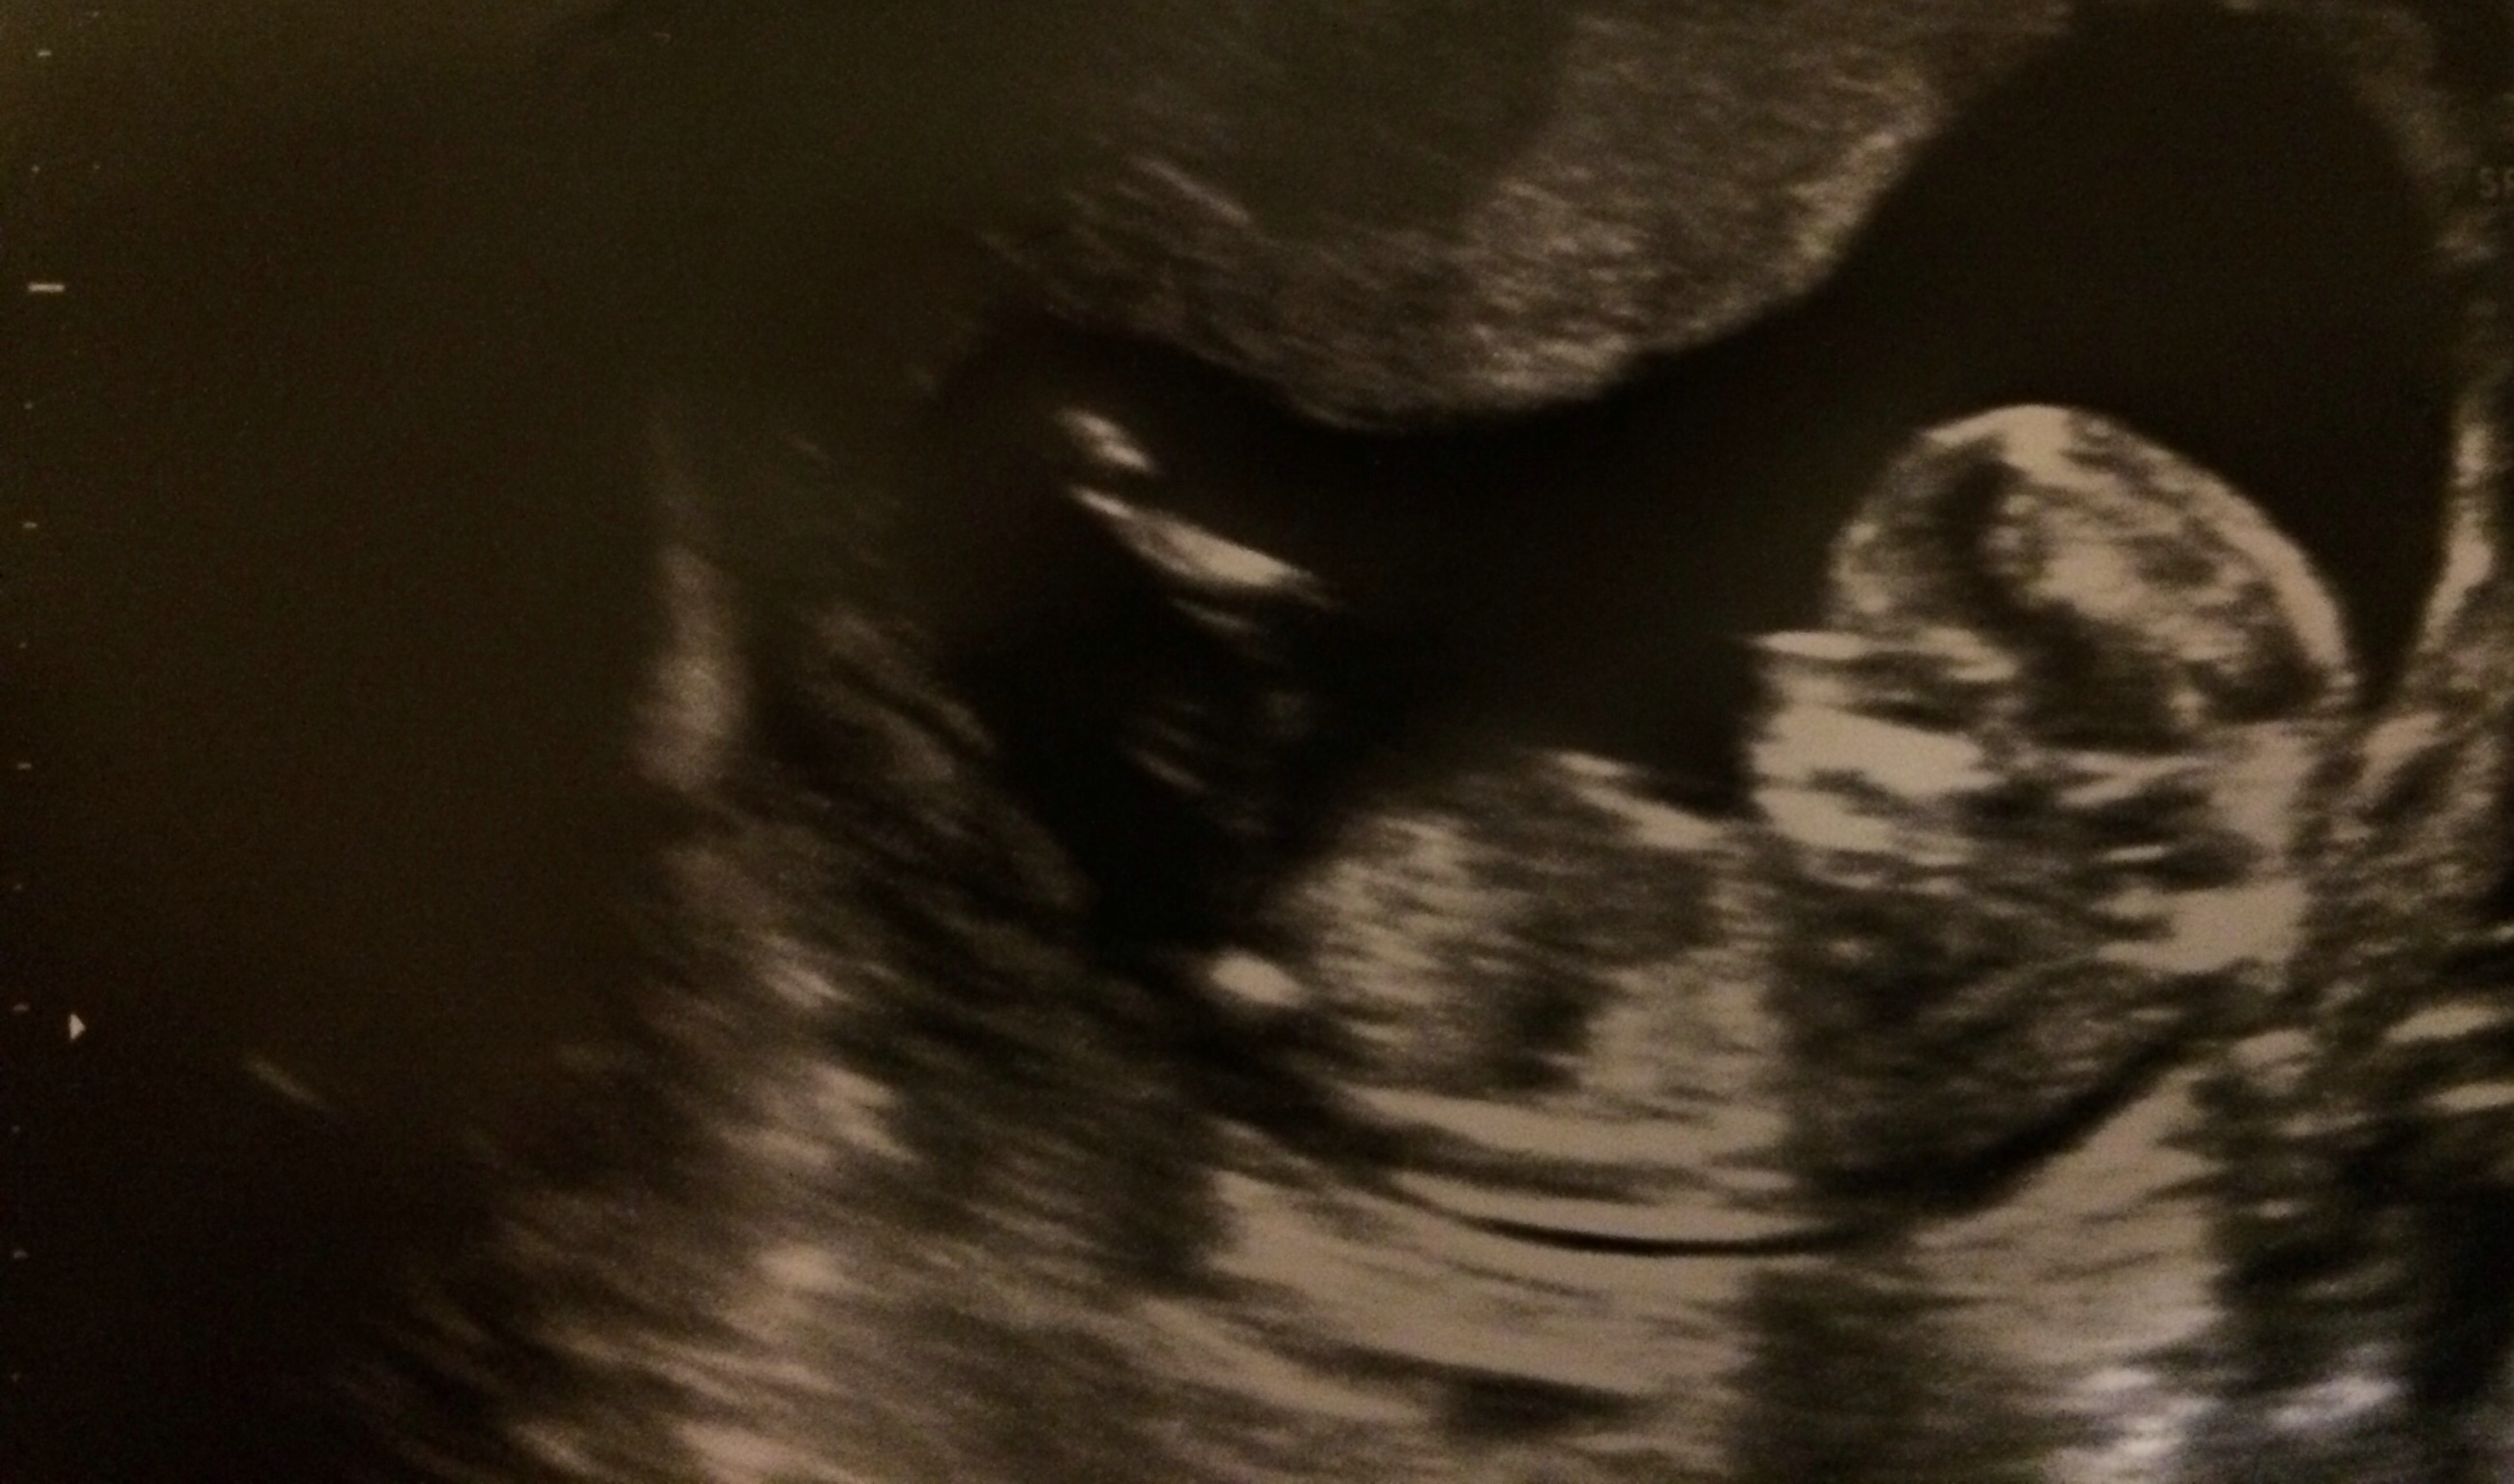

Baby is a bit too curled for my liking in both the shots that show any nub-action. My first thought was boy because of the end of the top nub. But given the curled baby, I wonder if I am seeing that because of how the spine is. I can't say I am leaning strongly either way. Sorry!